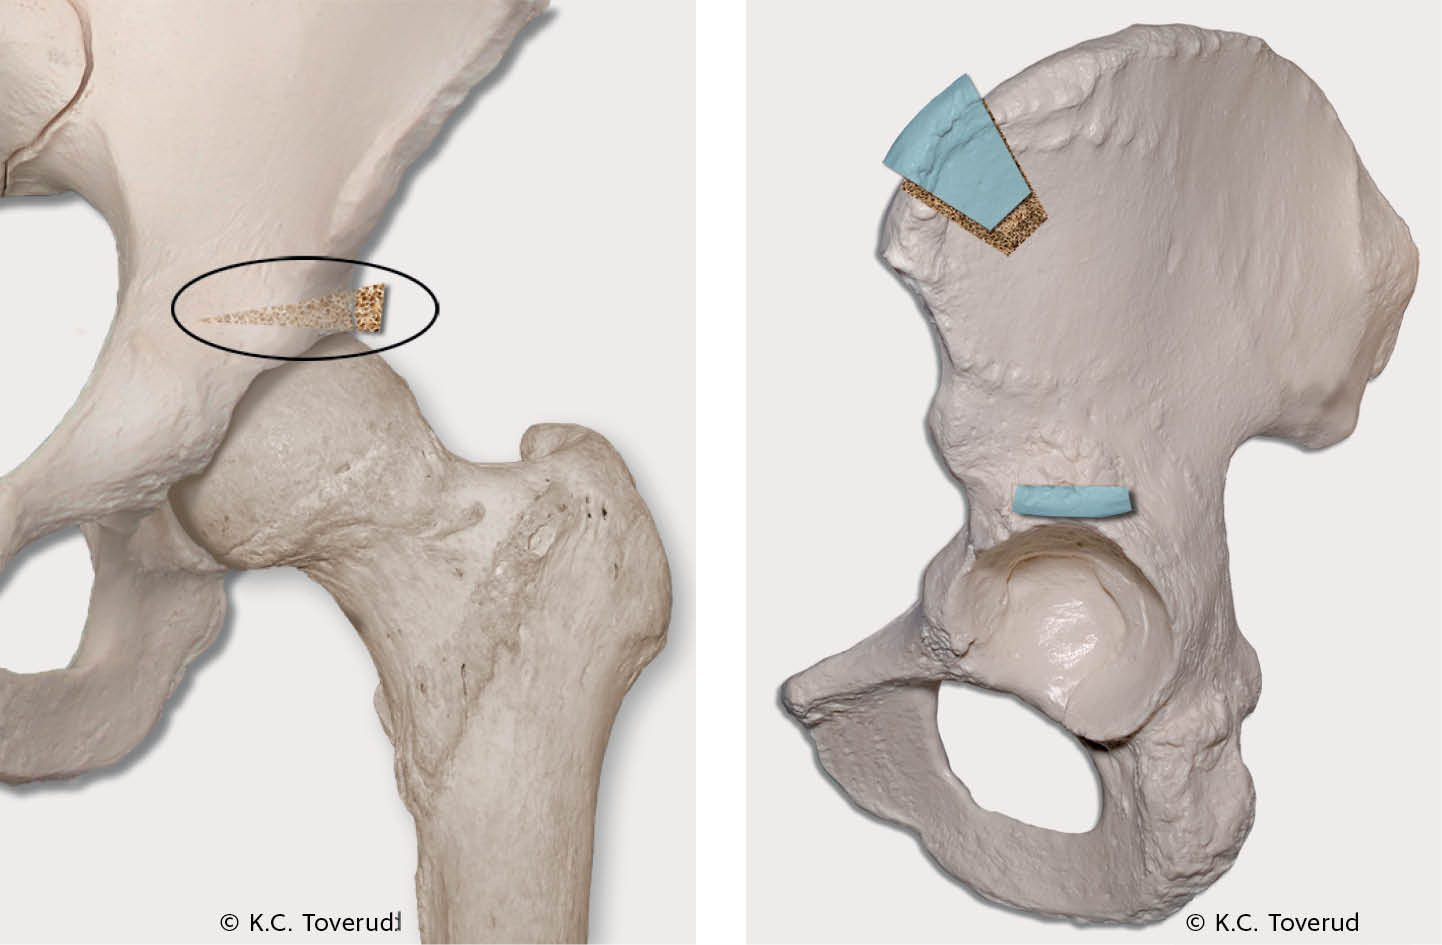

Ved andre hoftelidelser, spesielt hoftedysplasi og subluksasjoner, kan man gjøre bekkenosteotomier for å oppnå god caputdekning og leddstabilitet. Takplastikk, hvor acetabulums dekningsgrad økes ved bentransplantat som ved Spitzys prosedyre (figur 2), er et kirurgisk alternativ hos barn over åtte år (9). Fra 12-årsalderen og hos utvokste pasienter brukes oftest periacetabulær osteotomi (PAO) (10). Prosedyren går ut på reorientering av acetabulum for å gi bedre caputdekning (figur 3).